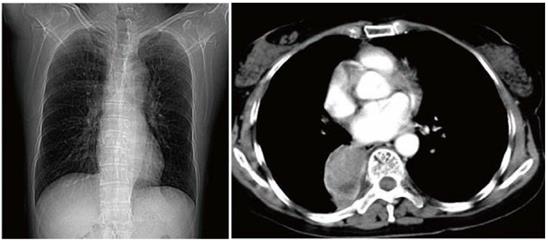

对于肺癌病灶的发现和特点的观察,胸部CT检查是较胸片更为先进的一种影像学检查方法。相较胸片而言,胸部CT可以发现正位胸片所难以发现的心脏后部病灶;同时,胸部CT检查可以使得直径小于1厘米的小结节肺癌病灶不易被漏诊;另外,胸部CT有助于医生判断肺部病灶的特点,例如病灶的外周是否光整,是否有毛刺,是否有分叶,病灶的内部是否有空洞,是否有钙化,病灶的周围是否有卫星结节等,这些特征的有无对于判断病灶的良、恶性,甚至是哪一种病因、哪一种类型,都是非常有帮助的。

胸部CT发现了胸部正位片难以发现的位于心脏后部的病灶